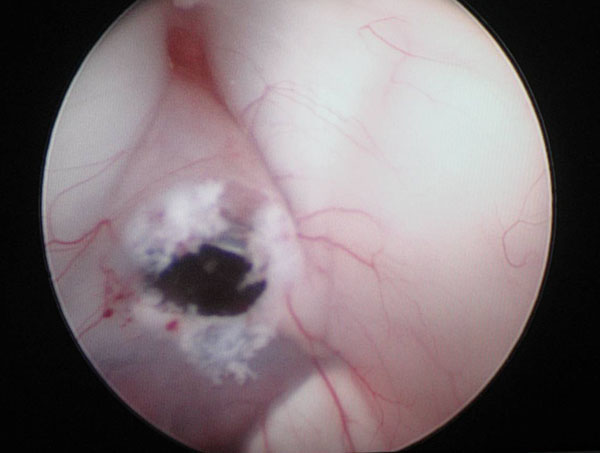

(内镜专家肖庆在手中 图片/神经外科)

神经内镜下脑室探查,相当于把神经外科医师的眼睛延伸到脑室内进行实地考察,可以发现头颅CT或磁共振检查难以发现的脑积水病因,并进行针对性的治疗。随着神经内镜设备及手术器械的不断改进与完善,手术创伤越来越小,效果越来越好,逐渐成为脑积水治疗的首选方式。

在神经内镜治疗脑积水时,软性电子内镜比硬质内镜相比更具有优势。软性电子内镜可以任意弯曲和变换方位,能够对脑脊液循环通路进行更大范围的探查与疏通,在更小的手术创伤下取得更好的效果。(东方红星 文/李烈 资料来源:航空总医院神经外科)